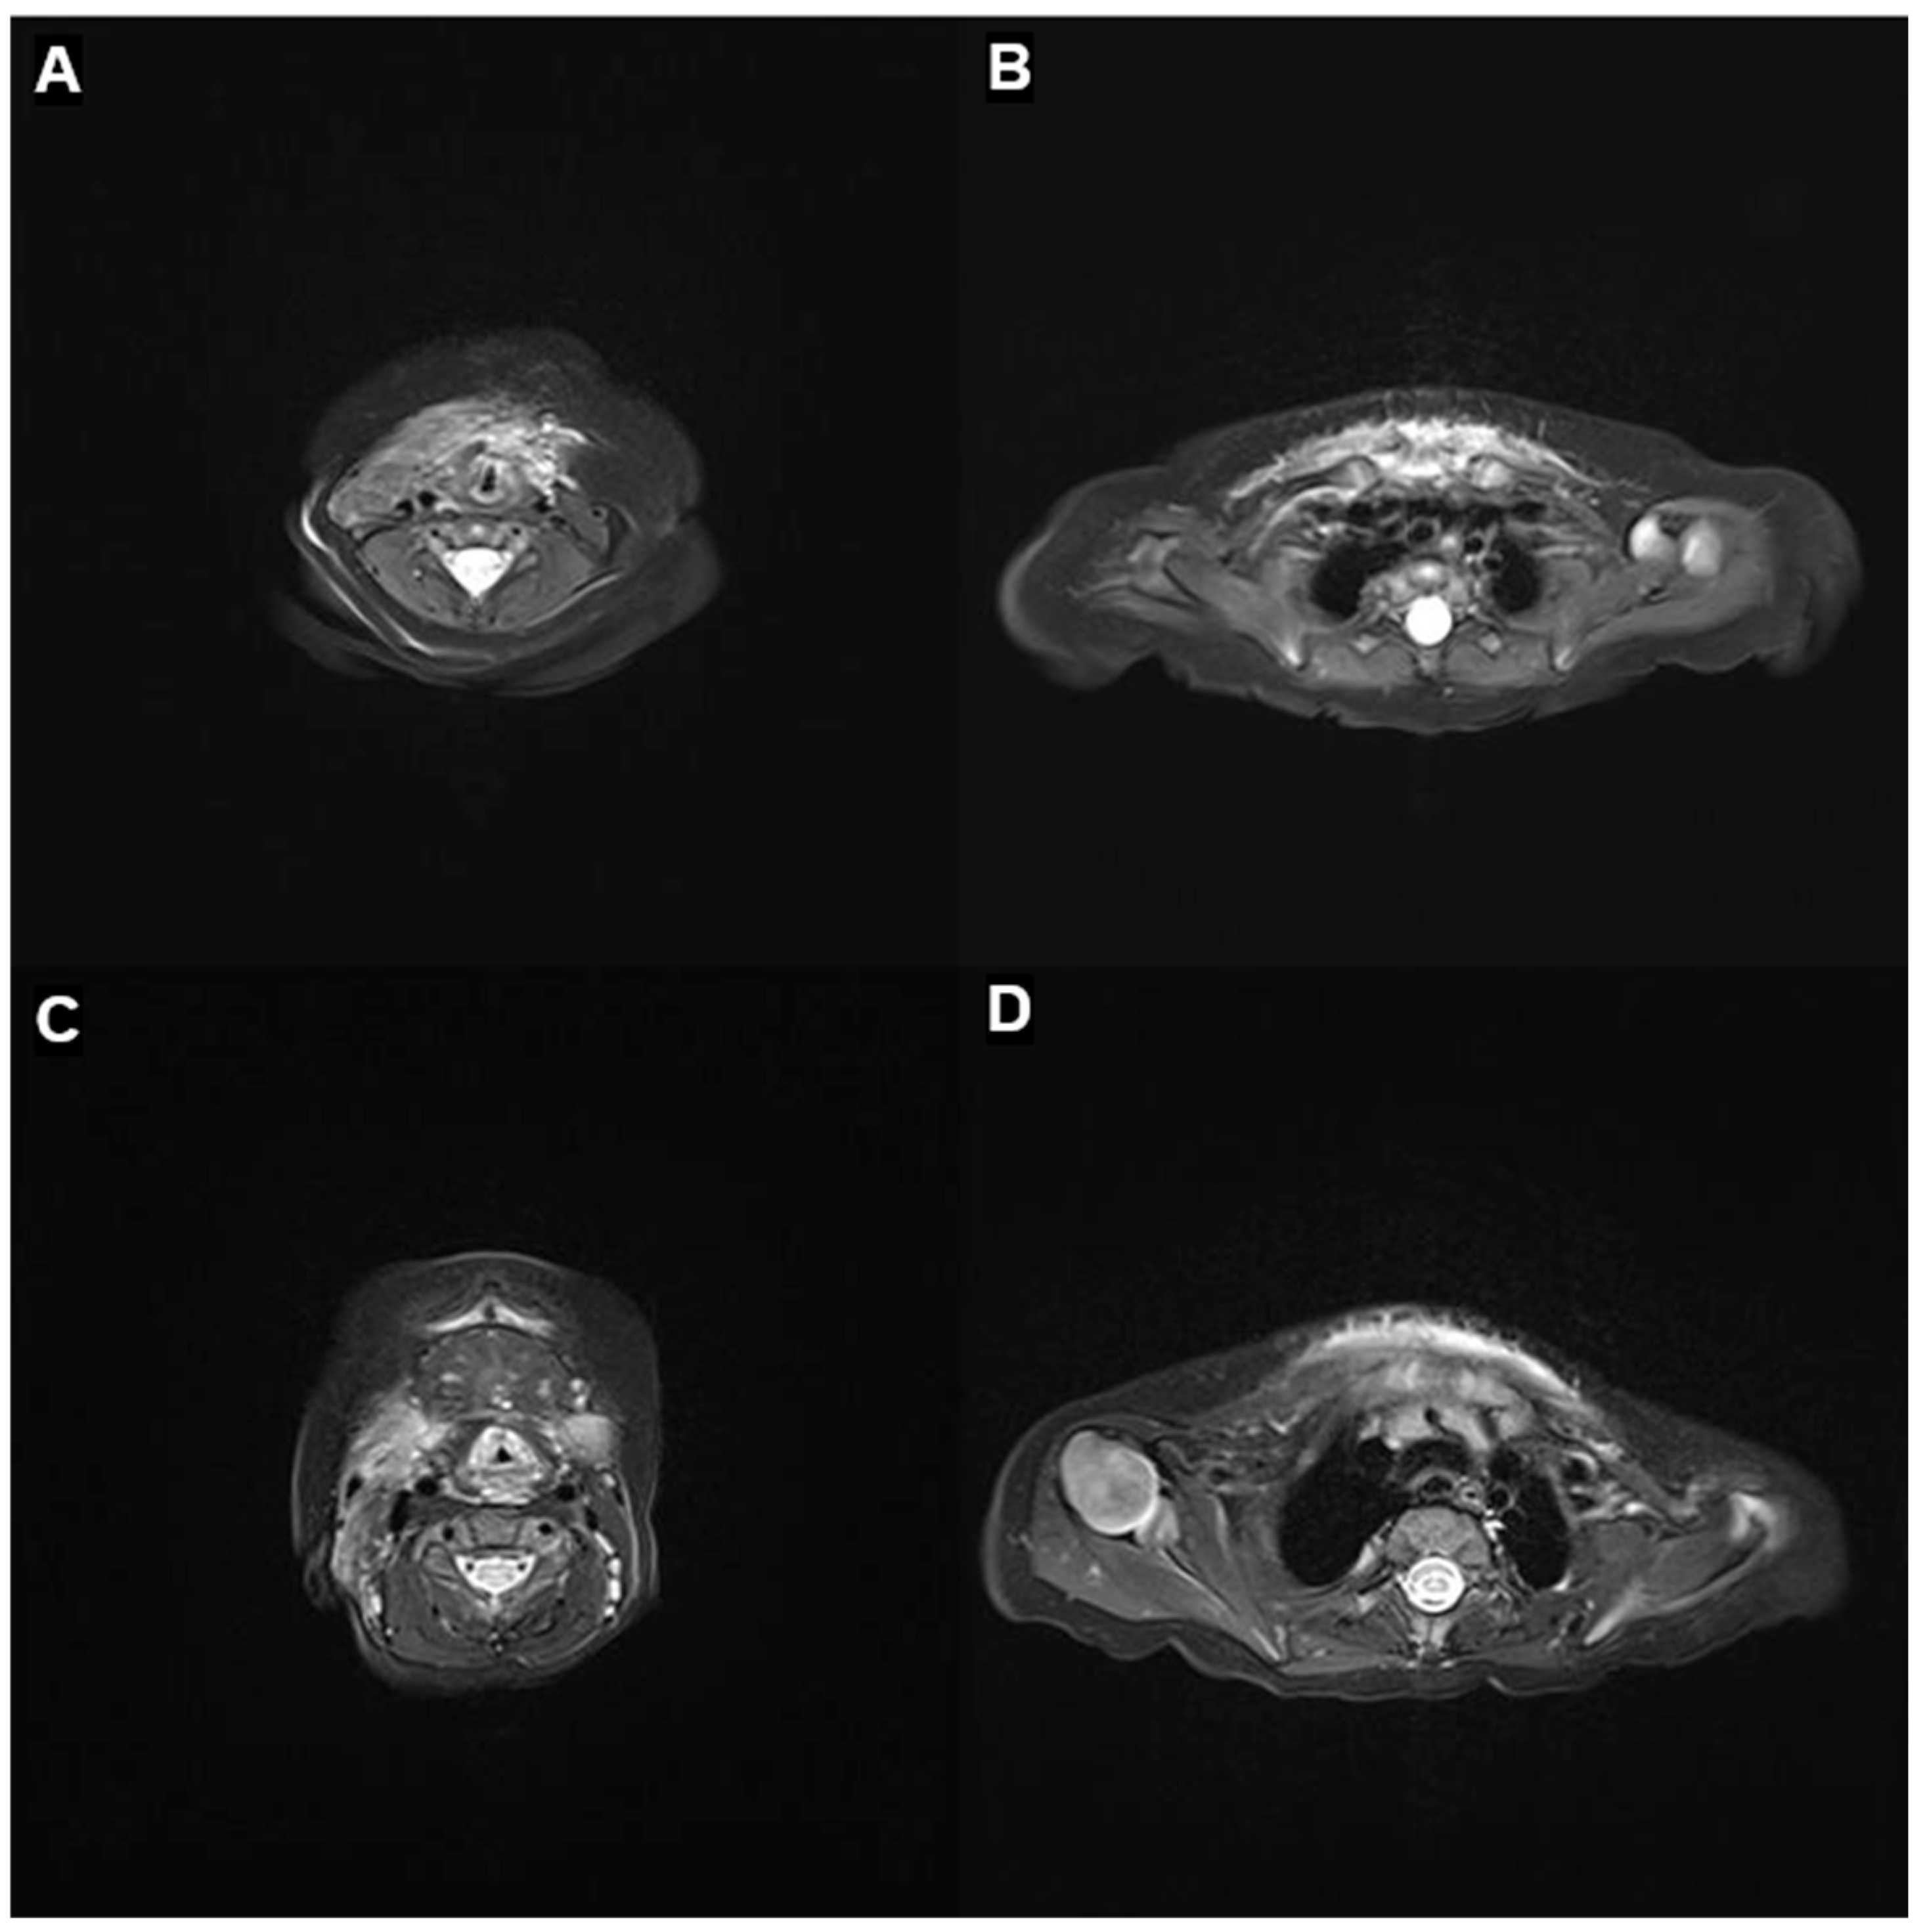

At 2 months of age, following clinical improvement and resolution of the acute phase, the patient was discharged from the NICU (Figure 1B). MRI of the neck and mediastinum performed at 3 months revealed a marked reduction in the hypervascular infiltrating lesion, extending from the infrahyoid level to the distal sternum, with preservation of the great vessels and no evidence of airway compromise (Figure 3A,B). At 9 months, MRI showed further regression with resolution of right parotid involvement but subtle residual lesions encircling the thoracic inlet in the lower neck and upper mediastinum, without airway obstruction (Figure 3C,D). At 1 year of age, clinical photographs demonstrated significant regression of the swelling with minimal residual deformity (Figure 1C). At the most recent follow-up at 16 months, the lesion remained stable without a transfusion requirement.

Figure 3.

Follow-up MRI after sirolimus therapy. (A,B) At 3 months of age, axial T2-weighted neck and mediastinal images show marked regression of the previously infiltrative hypervascular lesion, with residual involvement from the infrahyoid to the distal sternum. The great vessels are preserved in their normal positions. Several reactive lymph nodes are noted in the right level V, and subsegmental atelectasis persists in the left lower lobe. (C,D) At 9 months of age, axial T2-weighted neck and mediastinal images demonstrate further regression of the vascular tumor, including resolution of the right parotid involvement. A subtle residual lesion persists in the lower neck and upper mediastinum encircling the thoracic inlet, but without airway compression.